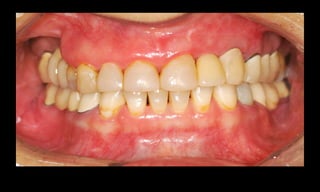

Resultados estéticos periimplantares otimizados

(Abboud, M. IJOMI, 2005).